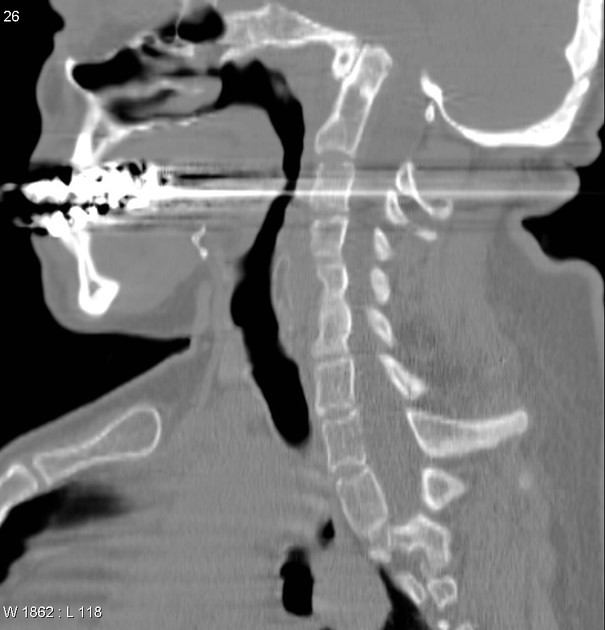

Crouzon syndrome

A

Abnormal calvarial shape: in severe case can give a “cloverleaf skull”

shallow orbits with exophthalmos

mid facial hypoplasia

bifid uvula

Associations

Chiari I malformations 3: may be present in ~70% of cases

hydrocephalus

stylohyoid ligament calcification: may be present in ~50% of patients over 4 years old 3

cervical spine abnormalities

cervical spine fusion

elbow malformations

hand deformities

agenesis of corpus callosum

How well did you know this?